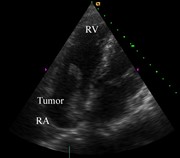

Right atrial myxoma with a large tumor embolus in the left pulmonary artery

Akihiko Ikeda and others

Journal of Surgical Case Reports, Volume 2014, Issue 10, October 2014, rju115, https://doi.org/10.1093/jscr/rju115